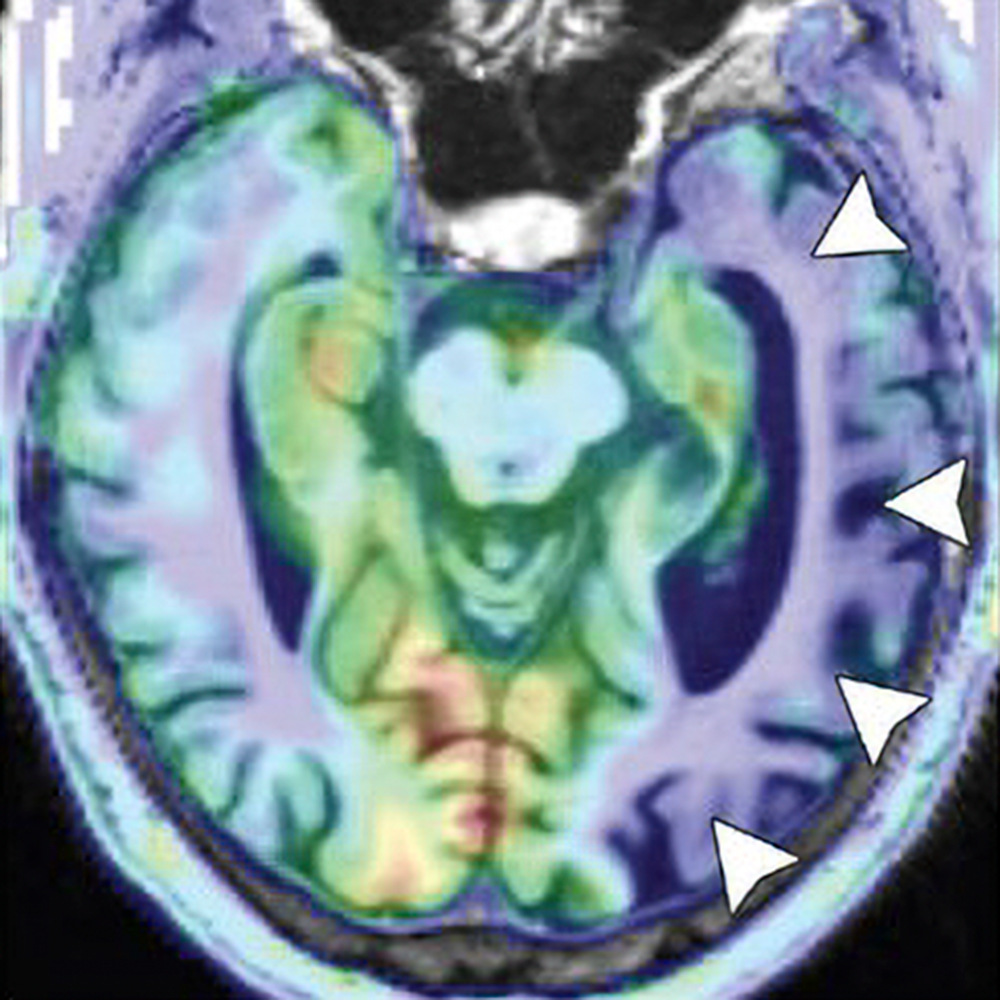

As TAVR becomes more common, the rad’s role is expanding from procedural planning to risk stratification.